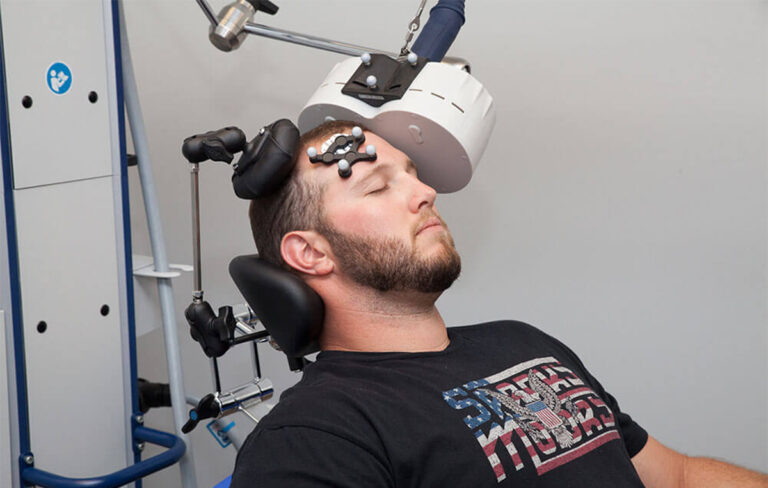

قیمت: 68٬000 تومان - دسته بندی فایل: علوم پزشکیپاورپوینت تی ام اس

فروش ویژه فایل های پاورپوینت حرفه ای تی ام اس با تخفیف استثنایی فقط 72000 هزار تومان تعداد اسلاید : 37 اسلاید